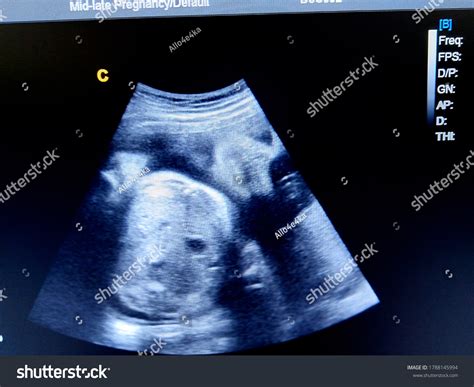

Pregnancy is an exciting journey filled with anticipation and wonder. One of the most crucial milestones in this journey is the 36 Weeks Sonography. This ultrasound scan, typically performed around the 36th week of pregnancy, provides valuable insights into the baby's development and the mother's health. Understanding the significance of this scan can help expectant parents prepare for the final stages of pregnancy and the upcoming birth.

The 36 Weeks Sonography is a routine ultrasound examination conducted to assess the baby's growth, position, and overall well-being. At this stage, the baby is fully developed, and the ultrasound can provide detailed information about the baby's readiness for birth. The scan is usually performed transabdominally, meaning the ultrasound probe is moved over the mother's abdomen.

The procedure is non-invasive and painless, similar to other ultrasound scans performed during pregnancy. The technician will apply a gel to the mother's abdomen and use a transducer to capture images of the baby. The entire process typically takes about 20-30 minutes.